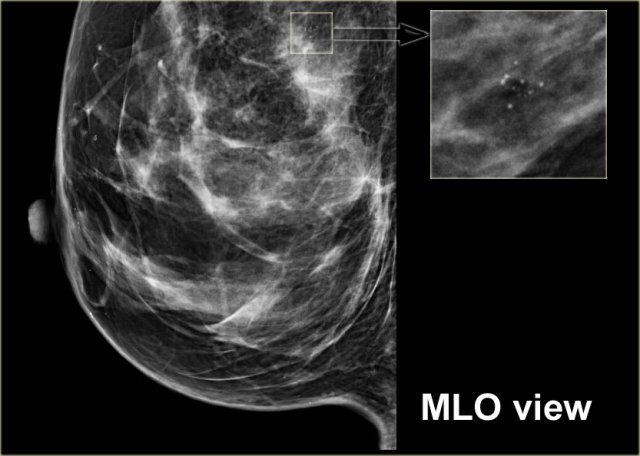

On the left calcifications in a segmental distribution.

Some have a linear distribution and some have a branching morphology.

This is highly suggestive of malignancy (Bi-RADS 4C).

High grade DCIS High grade DCIS

On the left fine linear and branching calcifications in a segmental distribution highly suggestive of malignancy (Bi-RADS 4C).

Extensive high grade DCIS was found at biopsy.